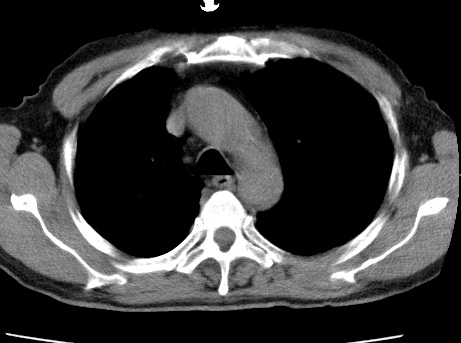

标题: CT24032:男65岁,咳嗽,吸烟20余年,无发热,咳痰 [打印本页]

标题: CT24032:男65岁,咳嗽,吸烟20余年,无发热,咳痰

考虑右肺中叶不张,请大家发表意见

右肺中叶不张、肺门轮廓增大,占位不除外;建议增强,必要时支气管镜详查。

右肺中叶支气管闭塞,中叶肺不张,右侧肺门见肿块影。中心型肺癌的可能大。建议支气管镜检查。

右中叶体积明显缩小,且其支气管未显示,先考虑:中心型肺癌班右中叶肺不张。

考虑右肺中叶中央型肺癌并右肺中叶肺不张;建议:行纤支镜检查。

右肺门旁类圆形肿块影,右肺中叶不张,建议纤支镜检查。

1右肺门旁类圆形肿块影,右肺中叶不张,建议纤支镜检查